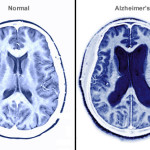

L’invecchiamento è un processo biologico complesso, accompagnato da un numero crescente di aggregati proteici tossici nelle cellule. Secondo gli scienziati, questi aggregati proteici tossici, sono tra le cause dello sviluppo di diverse malattie neurologiche come il morbo di alzheimr, parkinson e la malattia di Hintington.

” Questi risultati dimostrano che nelle cellule specificamente si accumulano proteine ricche di chaperone che fungono da meccanismo di sicurezza. Di conseguenza, gli aggregati sembrano essere una parte importante di un invecchiamento sano”, spiega Kasturi.” E’ noto infatti che gli aggregati proteici si accumulano nel cervello di anziani sani. Fino ad ora, gli scienziati hanno supposto che la neurodegenerazione e la demenza sembrano essere causate principalmente da specie di proteine aberranti che si accumulano in aggregati. Questa ipotesi potrebbe ora essere sconfessata.

” Risulta evidente che non tutti gli aggregati di proteine sono dannosi.Trovare il modo di concentrare proteine dannose in depositi insolubili, potrebbe essere una strategia utile per evitare o ritardare la malattia neurodegenerativa”, conclude il ricercatore.